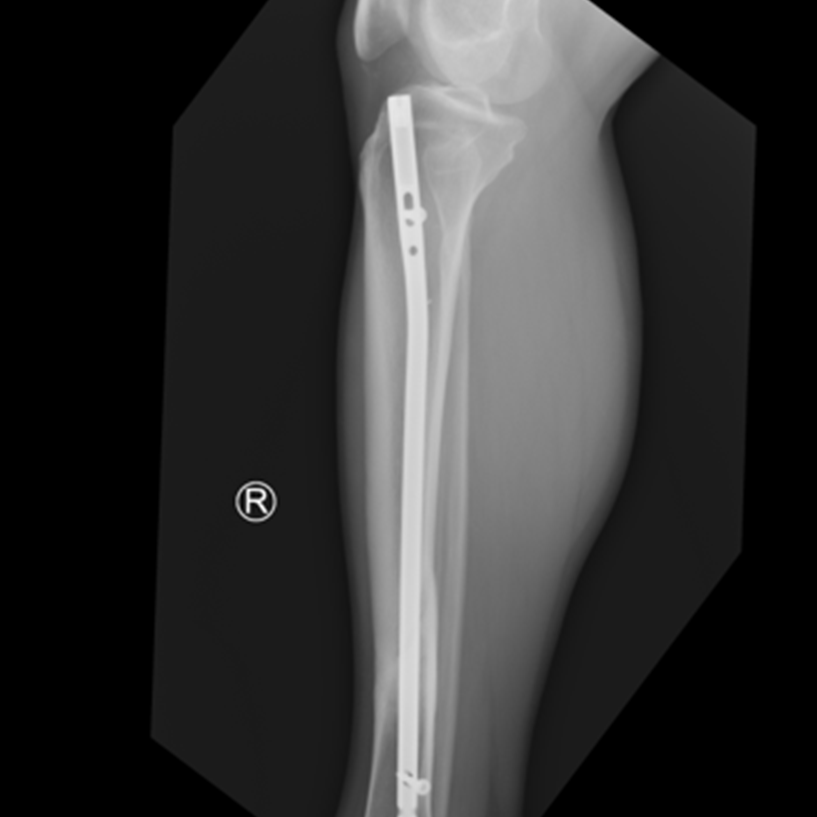

Zdjęcie 2.

Zdjęcia przedstawiają etapy gojenia (zrostu wtórnego), złamania kości piszczelowej zespolonej gwoździem śródszpikowym, od złamania do uzyskania zrostu.